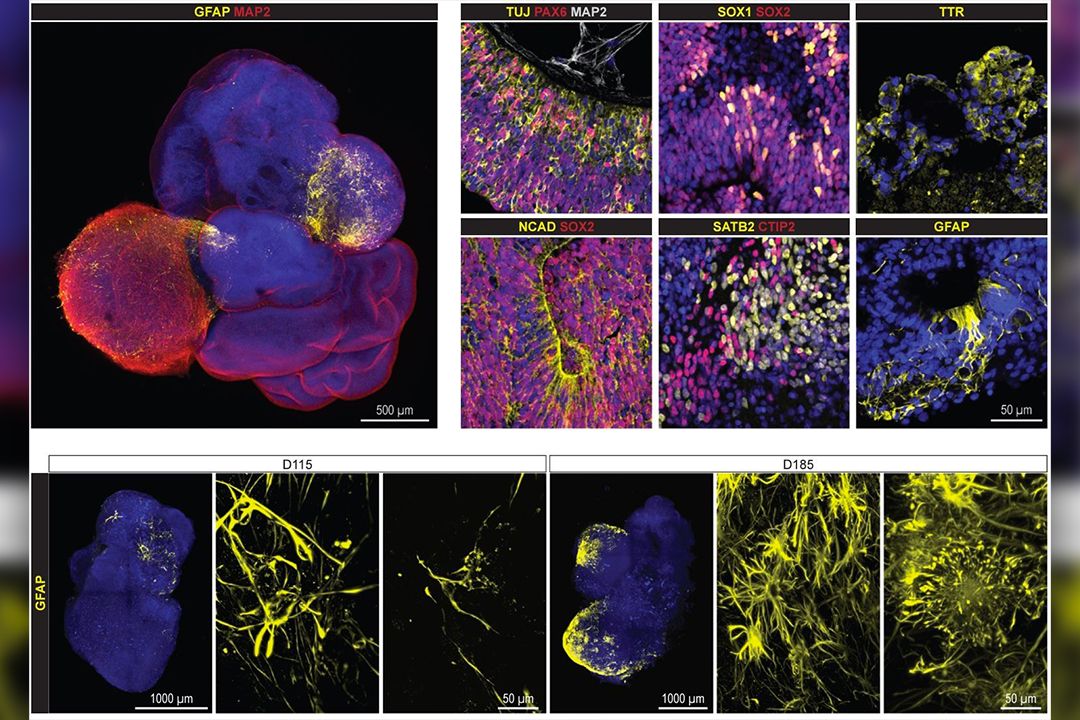

Vědkyně: Minimozky pomohou v testování léčby Alzheimerovy choroby

Genetika má na rozvoj Alzheimerovy nemoci silnější vliv než pouhé stárnutí. Ukázal to unikátní výzkum brněnských vědců, kteří vytvořili miniaturní verze mozků...

V Brně uměle vypěstovali minimozky s Alzheimerovou nemocí

Na laboratorně pěstovaných modelech mozku sledují výzkumníci z Lékařské fakulty Masarykovy univerzity v Brně rozvoj Alzheimerovy nemoci. Tzv. mozkové organoidy...